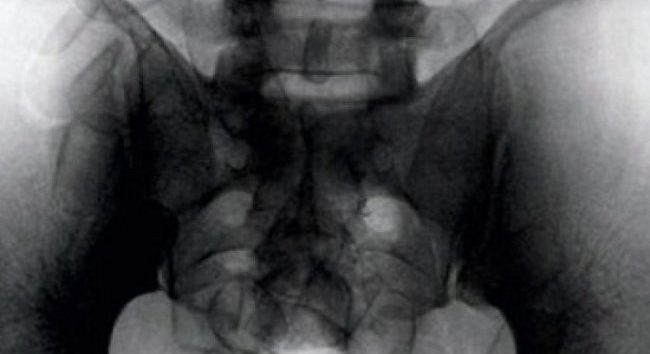

Un cittadino brasiliano è stato trattenuto diverse ore all’aeroporto di Malpensa per una sorta di “malinteso”. L’uomo, che mostrava durante un normale controllo un certo nervosismo e non aveva vestiti in valigia, è stato sottoposto ad un esame più approfondito. La radiografia ha mostrato nel suo intestino quelli che agli agenti, a prima vista, sono sembrati degli ovuli di coca.

Quando, il giorno seguente, il turista si è finalmente “liberato”, ecco la scoperta: non ovuli di cocaina ma dei normali fagioli. Tante scuse e l’uomo è stato lasciato andare.